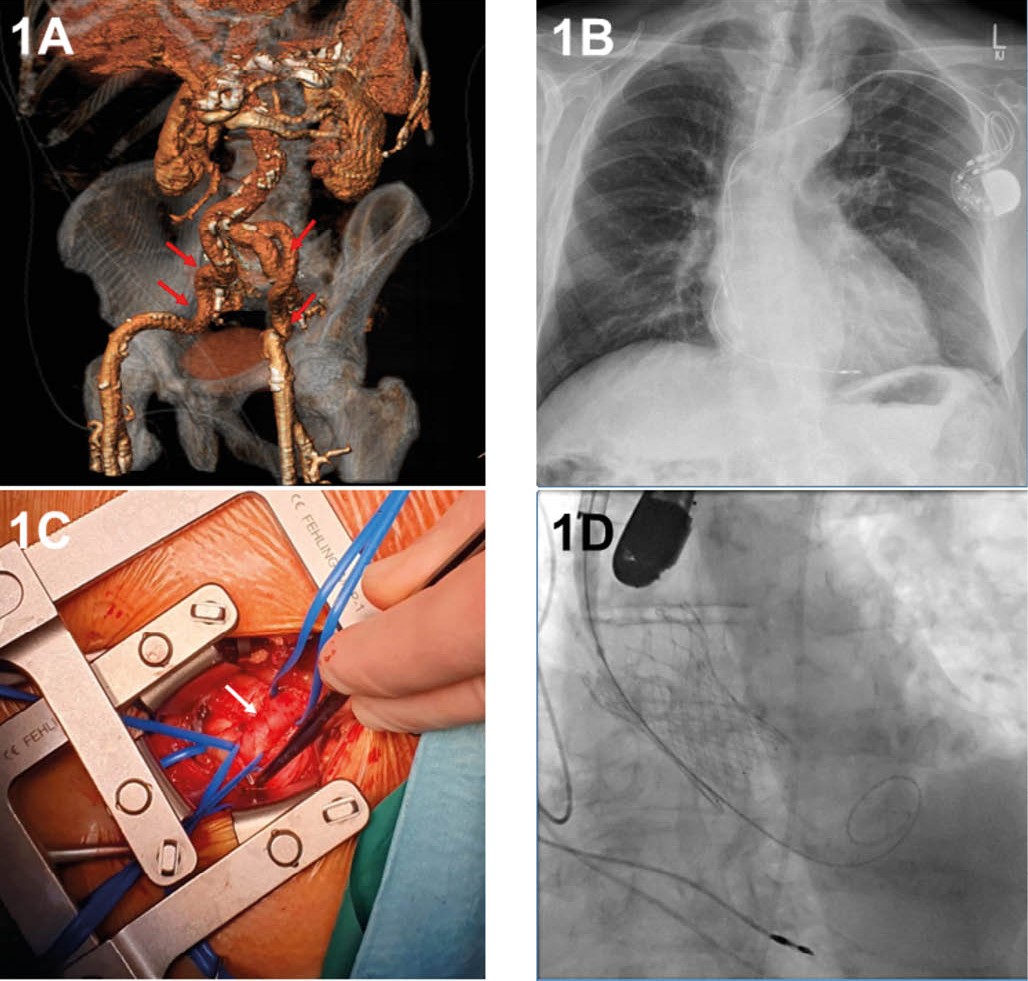

Eine 87-jährige Patientin wurde aufgrund ausgeprägter Belastungsdyspnoe (NYHA IV) und beidseitiger Unterschenkelödeme infolge einer schweren AS (AVPG (aortic valvular mean pressure gradient) 42 mmHg, Vmax 4 m/sec, AVA (aortic valve area) 0,5 cm²) aus einem peripheren Krankenhaus zur dringlichen TAVI übernommen. Das TAVI-CT zeigte einen größeren wandständigen Thrombus in der Aorta thoracica descendens (Abbildung V 3A & 3B). Aufgrund dieses Befundes wurde im Herzteam für den transaxillären Zugangsweg entschieden.

Die geplante Intervention wurde über den zuvor, wie oben beschrieben, etablierten transaxillären Zugang links durchgeführt, wobei diesmal eine ballonexpandierte Prothese verwendet wurde. Eine ballonexpandierbare Sapien S3, Größe 23 (Edwards Lifesciences Corp, Irvine, CA, USA), konnte erfolgreich über eine 14 French eSheath+-Schleuse (Edwards Lifesciences Corp, Irvine, CA, USA) implantiert werden (Abbildung V 3C). Sowohl die intraoperative TEE und angiographische Kontrolle als auch die postoperative TTE-Untersuchung bestätigten eine gute Klappenfunktion mit einem AV-Gradienten von max./mean 17/8 mmHg (Abbildung V 3D).

Aufgrund eines Sturzes mit Schädel-Hirn-Trauma während des Aufenthalts verzögerte sich die Entlassung der Patientin. Sie wurde am 26. postoperativen Tag in die Neurorehabilitation entlassen.

Abbildung V: Fall 3

3A: Angio-CT: Größer wandständiger Thrombus in der Aorta thoracica descendens (roter Pfeil).

3B: 3D-Darstellung der gesamten Aorta mit dem Thrombus (roter Pfeil) mittels 3mensio-System.

3C: Angiographische Aufnahme mit der implantierten Klappe (Sapien S3, Größe 23, (Edwards Lifesciences Corp, Irvine, CA, USA) (blauer Pfeil).

3D: Postoperative transthorakale echokardiographische Untersuchung mit guter Funktion der Klappe, ohne paravalvuläre Leckagen, Gradient max./mean 17/8 mmHg.

Fotos: Klinik für Herz- und Thoraxchirugie, Klinik für Kardiologie und Angiologie, Klinik für Radiologie, Universitätsklinikum Magdeburg